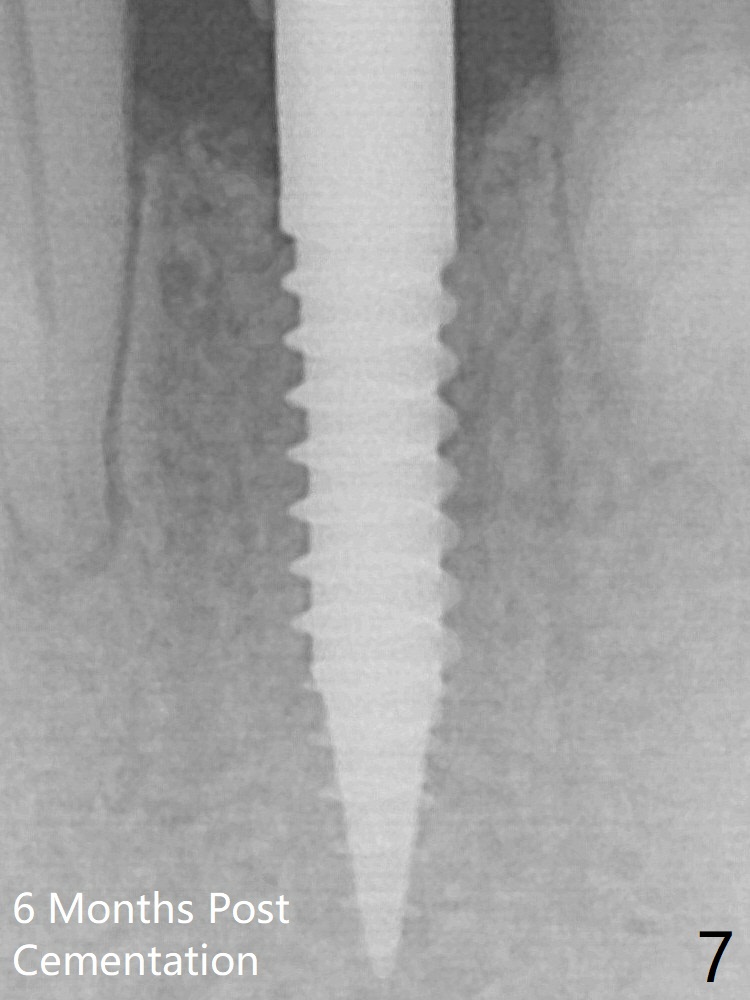

Since the gingiva is as thick as 7.5 mm (Fig.3 arrow), a 3x14 mm 1-piece implant with 4 mm cuff is placed (Fig.5); three implant threads are outside the native bone; with allograft (*) placed and the neighboring crests being coronal to the threads, the chance of periimplantitis should be remote. An immediate provisional is fabricated to contain the graft in place. The top 3 threads appear to be contacted by the newly formed crestal bone 6 months postop (Fig.6 *). Bone appears to have grown into the space between implant threads 6 months post cementation (13 months postop).